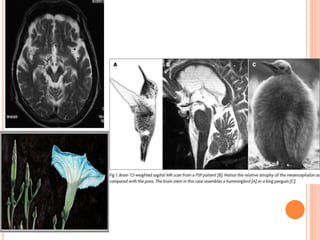

 MRI-

midbrain atrophy

Superior cerebellar peduncle atrophy.

“morning glory flower sign” and the “hummingbird sign” are

quite specific but show low sensitivity (50% and 68.4%,

respectively